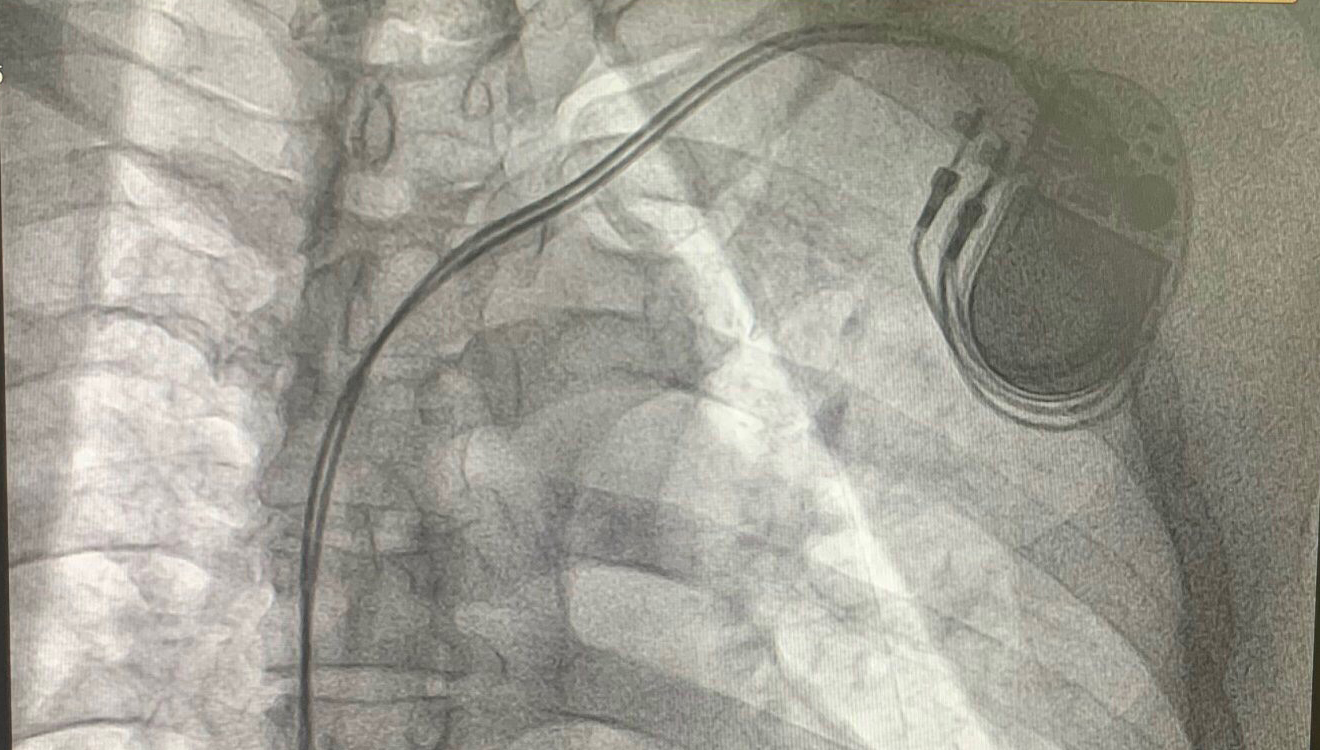

인공 심장 박동기 삽입술

인공 심장 박동기는 심장 박동을 조절하는 장치입니다. 이 장치는 심한 부정맥이 있는 경우에 사용됩니다. 가장 흔한 경우는 서맥과 심장 전도 차단입니다.

인공 심장 박동기는 제어 장치와 전극선의 두 부분으로 구성됩니다. 전극선의 한쪽 끝은 제어 장치에 연결됩니다. 다른 쪽 끝은 심방이나 심실에 부착됩니다. 제어 장치에는 배터리와 전기 회로가 들어 있습니다. 회로는 전기 자극 빈도를 조절할 수 있습니다. 덕분에 심장은 환자의 활동 요구에 맞는 빈도로 수축하게 됩니다.